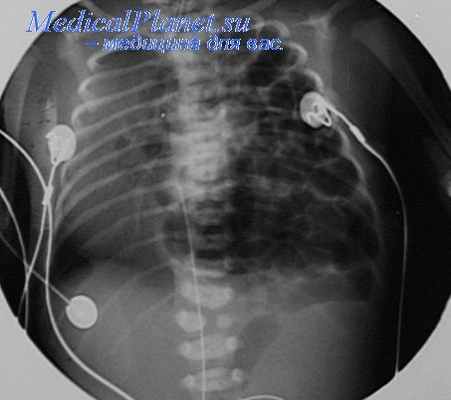

Диагноз диафрагмальной грыжи подтверждается обнаружением на рентгенограмме грудной клетки в прямой проекции множественных петель кишечника, наполненных газом, на стороне грыжи. Однако, если рентгенография делается до того, как воздух проник в кишечник, выявляются только смещение средостения, необычное расположение сердца и затемнение в одной половине грудной клетки.

Для подтверждения диагноза рентгенографию повторяют после введения через пазогастральный зонд воздуха или контрастного вещества.

После рождения диагноз ВДГ подтверждается после проведения комплексного УЗИ и рентгенографии органов грудной и брюшной полости.